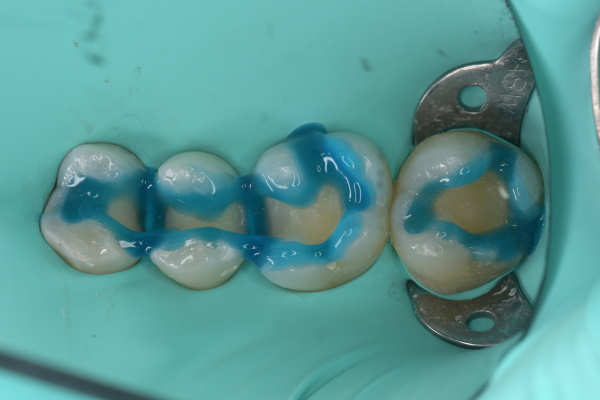

虫歯処置後

エッチング後